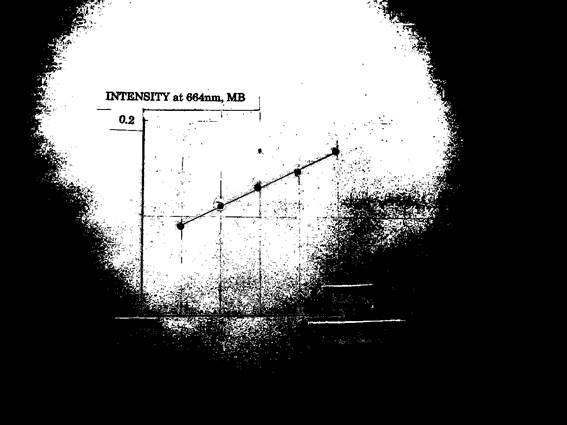

When hydrogen peroxide (oxygen-free radical) was added to this solution, oxidized MB increased gradually. This reaction is dependent on the concentrations of hydrogen peroxide which abstract electrons from leuco-MB ( Fig.3 ).

( Fig.3 )